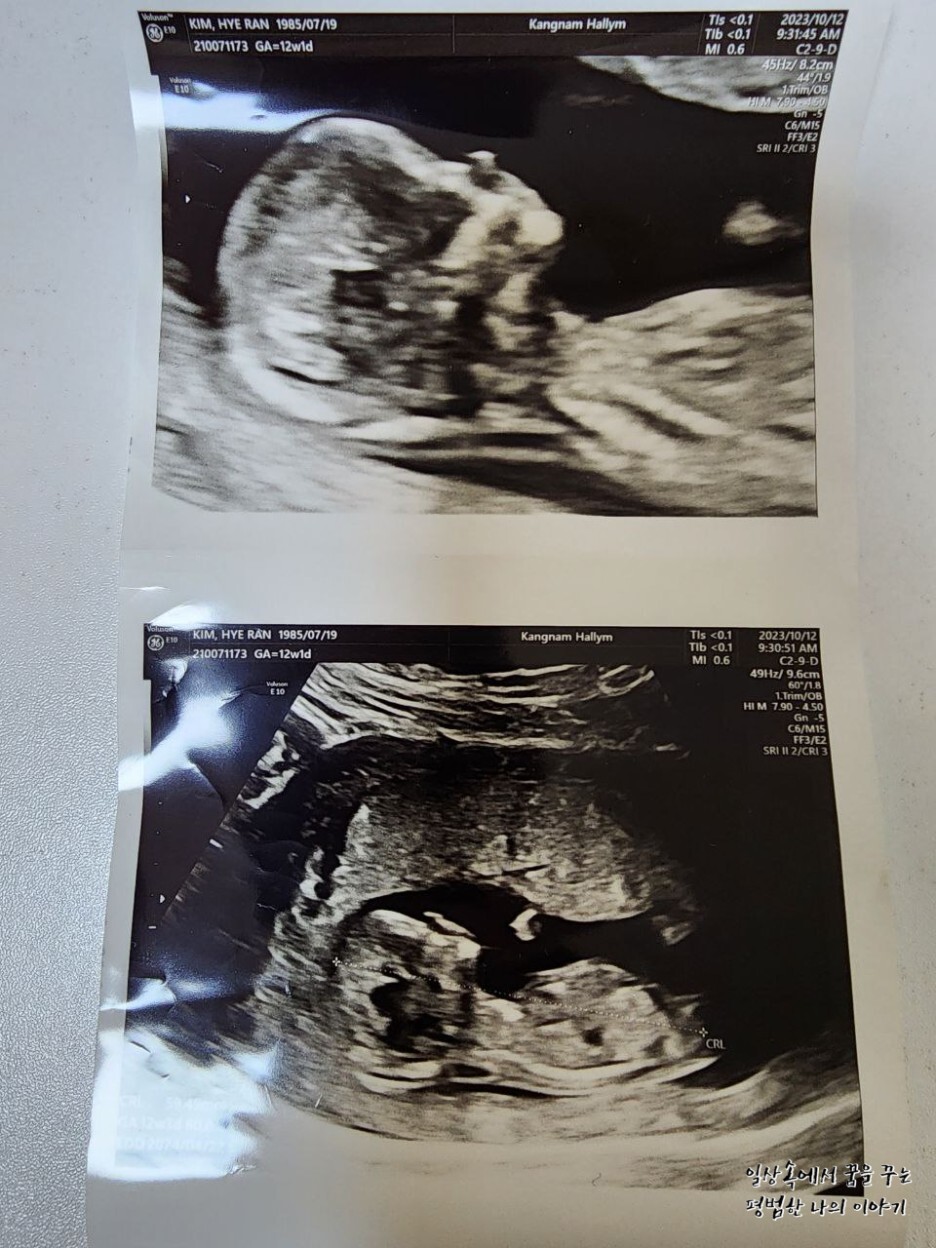

2023년 10월 12일(목요일)

EDD(Expected Date of Delivery, 출산 예정일): 2024년 4월 22일

FHR(Fetal Heart Rate, 심장박동 수): 167bpm

CRL(Crown-Rump Length, 태아의 머리부터 엉덩이까지의 길이): 59.49mm

소견: 1차 기형아 검사 목 투명대랑 콧대 모두 정상으로 나옴 / 니프트(NIFT) 피검사함(결과는 2~3주 뒤 나옴)

아기의 크기는 고작 59.49mm이지만 벌써 어느 정도 사람의 형태를 하고 있기 때문에 볼 때마다 신기할 따름이다. 특히나 다리랑 팔의 형태가 지난번에 비해 많이 뚜렷해졌다. 병원에서 12주 차부터 아기의 성별을 알려주시기도 하는데 하도 움직임이 많은 아기라 아들인지 딸인지 확인이 어렵다고 하셔서 다음을 기약하기로... 엄마는 아들이든 딸이든 다 좋아! 참고로 아빠는 딸이었으면 좋겠데! 아기를 낳고 키워보니 정말 다른 거 다 필요 없고 건강하게만 태어나고 자라주는 것이 최고의 복인 것 같더라.